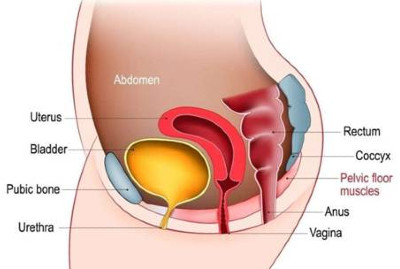

Είναι το συχνότερο είδος ακράτειας στις γυναίκες και οφείλεται στην χαλάρωση του πυελικού εδάφους (Εικ.1) αλλά και στην εμμηνόπαυση.

Εικ.1: Το γυναικείο Πυελικό Έδαφος